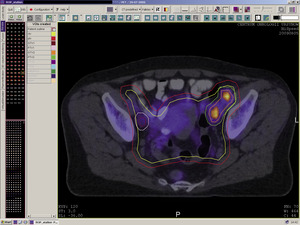

Rycina 1. Trójwymiarowa rekonstrukcja wyznaczonych objętości do napromieniania i wybranych narządów krytycznych w planowaniu radioterapii 3D chorej na raka szyjki macicy.

Teleradioterapia, napromienianie wiązkami zewnętrznymi, jest prowadzona głównie przy użyciu wysokoenergetycznych fotonów X, generowanych w przyspieszaczach liniowych. W wybranych sytuacjach mają też zastosowanie wiązki elektronów o różnie dobieranych energiach. Coraz rzadziej stosowane jest promieniowanie gamma kobaltu 60. Postęp technologiczny i dostępność komputerowych systemów planowania przestrzennego radioterapii, opartych na nowoczesnych technikach obrazowania, umożliwiły w większości ośrodków planowanie radioterapii dostosowawczej (konformalnej), realizowanej według indywidualnie przygotowanych planów leczenia. Planowanie pól napromieniania odbywa się przestrzennie – trójwymiarowo (3D), z wykorzystaniem przekrojów tomografii komputerowej, na których lekarz oznacza guz nowotworowy, elektywny obszar do napromienienia (regionalne węzły chłonne z adekwatnym marginesem) i narządy krytyczne (ryc. 1). W wybranych przypadkach w planowaniu wykorzystuje się połączenia obrazów z badaniem pozytonową tomografią emisyjną (PET-TK), co daje możliwość zwiększenia dawki w obszarze dużej aktywności metabolicznej guza nowotworowego lub jego przerzutów do regionalnych węzłów chłonnych (ryc. 2).1,2 Za pomocą komputerowych systemów planowania leczenia fizyk tworzy indywidualny plan leczenia, który powinien spełniać kryteria jednorodnego rozkładu dawki promieniowania w planowanej objętości napromienianej (PTV) oraz dużego gradientu dawki poza tą objętością. Jednocześnie nie należy przekraczać ustalonych dawek tolerancji w narządach krytycznych (OR) (ryc. 3). Dopasowanie kształtu pola napromieniania do konturu planowanej objętości napromienianej osiąga się, stosując kolimatory wielolistkowe o zmiennym kształcie. Poprawność planowania radioterapii oparta na kryteriach zebranych w raportach 50 i 62 International Commission on Radiation Units (ICRU) dokumentują histogramy rozkładu dawki promieniowania w planowanej objętości i w wybranych narządach krytycznych (ryc. 4). Ośrodki wyposażone w nowoczesne wysokoenergetyczne przyspieszacze liniowe i wysoko wydajne systemy planowania radioterapii mogą stosować radioterapię z użyciem modulacji intensywności dawki promieniowania (intensity modulated radiation therapy, IMRT). Główną zaletą tej techniki jest możliwość modelowania dawki całkowitej promieniowania w obszarze napromienianym z oszczędzeniem struktur krytycznych (ryc. 5).3 Technika dwuwymiarowa (2D) stosowana jest nadal z powodzeniem w przypadkach leczenia paliatywnego. Stosuje się wówczas najprostsze techniki dwu pól przeciwległych i czteropolową technikę „box”, polegającą na napromienianiu odpowiednio na dwa lub cztery pola wlotowe, których płaszczyzny są parami równolegle. Powyższe napromienianie nie gwarantuje jednak jednorodnego rozkładu dawki promieniowania w wyznaczonej objętości. Stwarza ono też ryzyko przedawkowania ponad należną dawkę promieniowania w obrębie narządów krytycznych.